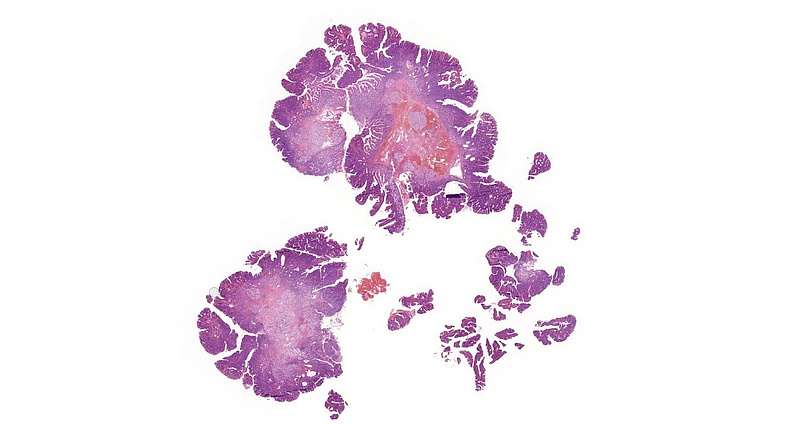

A 60-year-old female patient underwent multiple gastroscopies during the last 5 years because of recurring jaundice. Biopsy samples of the Vater papilla were taken each time, showing tubular or tubulovillous adenomatous growth. In 2021, the lesion was resected in toto with sphincteroplasty. Microscopic examination of this sample revealed tubular and tubulovillous structures, showing signs of low-grade dysplasia (revised Vienna classification category 3) in continuation with normal mucosa [Panels A-D]. Brunner glands were present in the submucosa. Even though the resection margin was free of dysplasia and invasive malignancy not detected, careful follow-up was recommended due to the patient’s history and the recurring nature of the lesion.